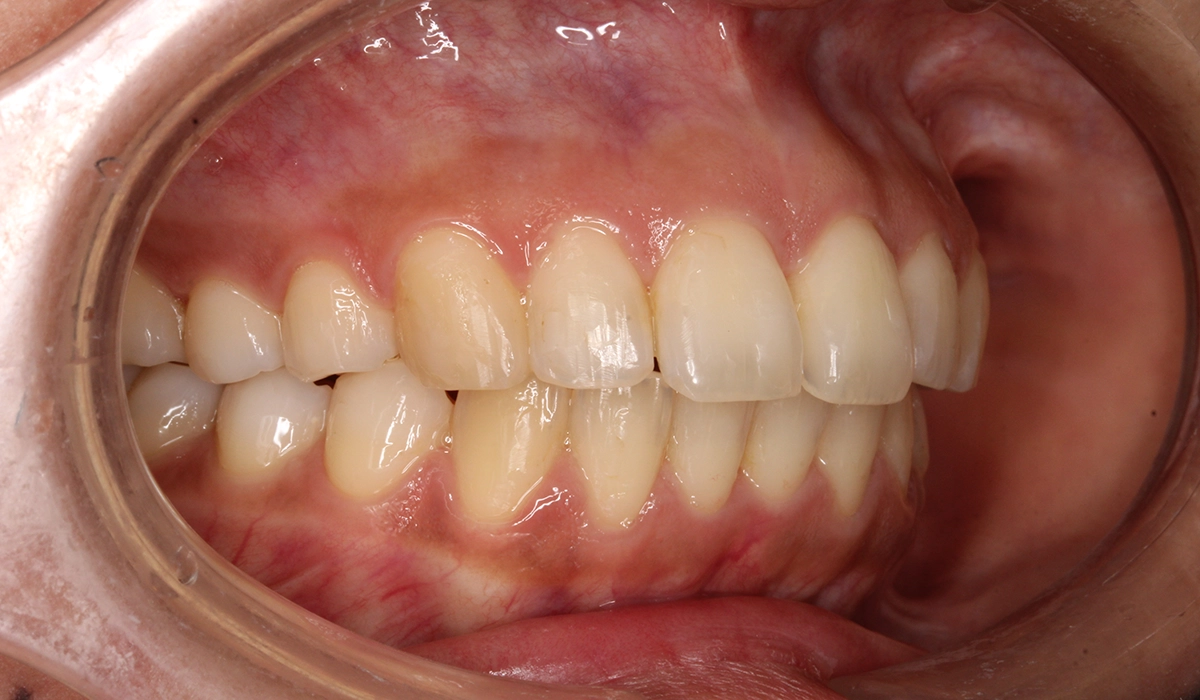

術後:右側

術後:左側

| 治療期間 | 18カ月 |

| 治療内容 | 上下前歯部のがたつきを気にされており、検査後Ⅰ級叢生と診断いたしました。左上7番予後不良により抜歯し、左上8番を配列したためやや治療期間が長くなるも満足いく配列となり患者様も満足していただけました。 |